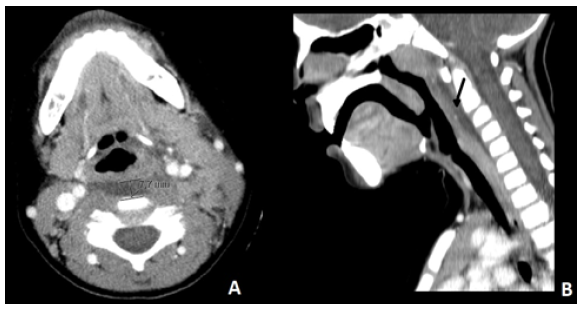

Cervical ultrasound showed an aggregate of multiple pericentimetric lymph nodes, with adjacent fat densification and no signs of necrosis. Cervical computed tomography (CT) revealed an enlarged left palatine tonsil without contrast enhancement, compatible with tonsillitis, with multiple reactive lymphadenopathies in the left internal jugular chain and left retropharyngeal space, one of which with initial signs of liquefaction (Figure 1-A). Liquid infiltration with a maximum thickness of 8 mm in axial plane was noted in the retropharyngeal space, suggesting an early retropharyngeal abscess (Figure 1-B).

Figure 1 Cervical CT scan showing liquid infiltration in the retropharyngeal space suggestive of an initial retropharyngeal abscess. (A) Axial plan, with a maximum thickness of 8 mm. (B) Sagittal plan (arrow).